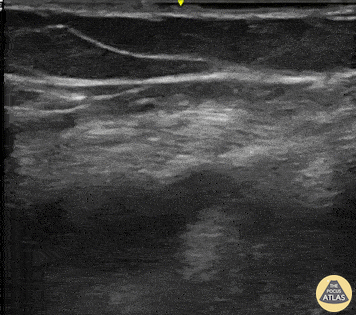

A 45-year-old female presented to the ED with chest pain, dyspnea, and evidence of shock. Our FOCUS cardiac exam was notable for acute pulmonary hypertension. Subsequently using our multi-organ approach we identified evidence of a DVT (linear probe on the proximal left leg reveals hyperechoic material within the non-compressible femoral vein). Diagnosis of pulmonary thromboembolism secondary to VTE causing obstructive shock was immediately confirmed at the bedside. Images from: Emergency Department of Marilia Clinic Hospital, Sao Paulo, Brazil. POCUSJEDI Team. @JediPocus